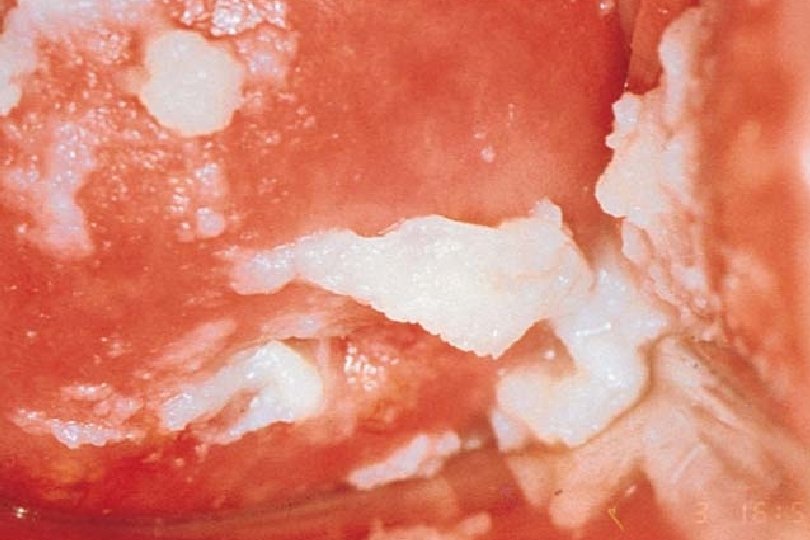

Vulvovaginal Candidasis: The Basics · · · Candida albicans >90% (others <10%, esp. C. glabrata) - Normal vaginal flora - Colonic reservoir Not sexually transmitted, although male partners sometimes get superficial balanitis, especially in uncircumcised Diagnosis: Clinical appearance, low p. H, no odor, microscopy

Vulvovaginal Candidiasis · · · Vulvar component often dominant Most cases still caused by C. albicans (>90%) Women are often misdiagnosed as having VVC when they really have - · Genital herpes Lichen planus Recurrent BV - Contact dermatitis - Atrophic vaginitis Uncomplicated VVC defined by all 4: - Sporadic Mild-moderate severity Likely to be Candida albicans Non-immunocompromised host Sobel JD, Lancet 2007

Diagnosis of VVC · · Clinical appearance and symptoms - Typically prominent irritative symptoms - Minimal discharge Laboratory - p. H <4. 5 - Negative amine odor - Microscopy (KOH preparation, Gram stain) - Isolation of Candida species usually not helpful • Nonspecific owing to asymptomatic carriage by most women some of the time and some women all of the time • C. albicans is normal vaginal flora